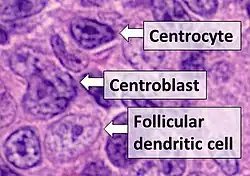

The diagnosis of FL depends on examining involved tissues for histological, immunological, and chromosomal abnormalities that are indicative of the disease. FL usually involves enlarged lymph nodes populated by abnormal follicles (see adjacent picture) that when examined histologically contain a mixture of centrocytes or centroblast surrounded by non-malignant cells, mostly T-cells. The centrocytes, which typically outnumber centroblasts, are small to medium-sized B-cell lymphocytes that characteristically exhibit cleaved nuclei; the centropblasts are larger B-cell lymphocytes without cleaved nuclei.[9] Rare cases of FL may show lesions that contain tissue infiltrations dominated by B-cells with features of precursor (i.e. "blast") cells, monocytes, or malignant mantle cells such as those found in mantle cell lymphoma.[1] Immunochemical analyses reveal that these cells generally express B-cell surface markers including the CD10 (60% of cases), CD20, CD19, CD22, and CD79 but not CD5, CD11c, or CD23 cell surface proteins;[2] genomic analyses reveal that these cells contain t(14:18)(q32:q21.3) translocation (85–90% of cases), 1p36 deletions (60–70% of cases), and with far less frequency the other genomic abnormalities listed in the above sections on Pathophysiology and Presentation and course. None of these protein markers or genomic abnormalities are diagnostic for FL, e.g. the t(14:18)(q32:q21.3) translocation is found in 30% of diffuse large B-cell lymphoma and in a small number of reactive benign lymph nodes. Rather, the diagnosis is made by a combination of histological, immunological, and genomic abnormalities.[2] According to World Health Organization (WHO) criteria, follicular lymphoma can be classified morphologically by the relative amount of centroblasts. However, such classification is optional, due to poor reproducibility and little difference in prognosis and treatment, except that a lymphoma with almost only centroblasts may be diagnosed as a diffuse large B-cell lymphoma (DLBCL).[48] The optional classification of follicular lymphoma is as follows:[49]

- Centrocytes are small to medium size with angulated, elongated, cleaved, or twisted nuclei.

- Centroblasts are larger cells containing vesicular nuclei with one to three basophilic nucleoli apposing the nuclear membrane.

- Follicular dendritic cells have round nuclei, centrally located nucleoli, bland and dispersed chromatin, and flattening of adjacent nuclear membrane.